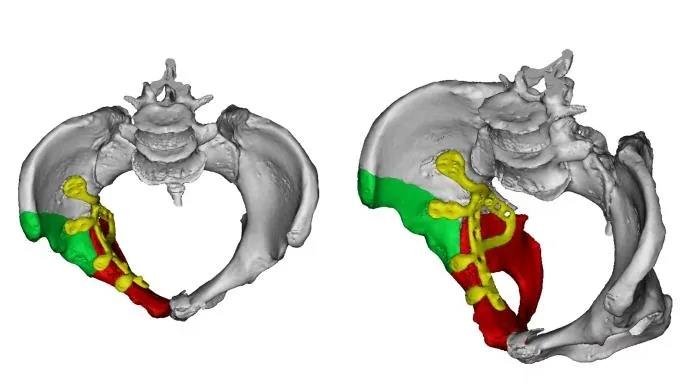

术前,骨盆科团队在我院3D实验室的支持下,为韦阿姨量身定制了1:1骨盆骨折模型及右侧半骨盆镜像对称模型,通过物理拼装与数字化模拟,详细了解骨折情况,进行手术预演,利用3D打印技术进行数学化模拟复位,精准规划钢板放置的位置与螺钉走向,这一“实体+数字”双模态规划,为手术提供了坚实保障,真正实现“术前有预案,术中零盲区”。

▲吕广桂医生利用3D模型进行手术预演

▲在3D实验室术前模拟

立项科研“3D打印在骨盆髋臼骨折的应用”:体外预先模拟手术,为骨盆髋臼骨折患者科学制定更精准的手术规划,提高骨折复位、固定的精确度和手术的安全性,使患者术后获得更好的疗效。